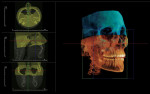

Many CBCT units have a variable FOV that allows the clinician to limit the radiation exposure to the region of interest. The limiting factor is the size of the image detector, which varies depending on the manufacturer, but for the sake of simplicity, this article will discuss them in categories—small (< 6 in), medium (6 in), large (9 in), and extra-large (12 in) FOVs (Figure 2 and Figure 3). The maximum image of a small FOV usually can accommodate several teeth or a sextant of an arch. The maximum medium FOV can accommodate the normal adult dentition, and the maximum large FOV encompasses the maxillofacial anatomy including the condyles and most of the orbits. Finally, the extra-large FOV can accommodate the full skull in most cases. Regardless of the volume capacity of the unit, it is important to restrict the FOV to the region of interest, which has a significant effect on the amount of radiation absorbed.23

It is important to note that the various CBCT units come with standard viewing software, which will allow the dentist to examine the selected area of interest in all three planes: axial, coronal, and sagittal (Figure 5).